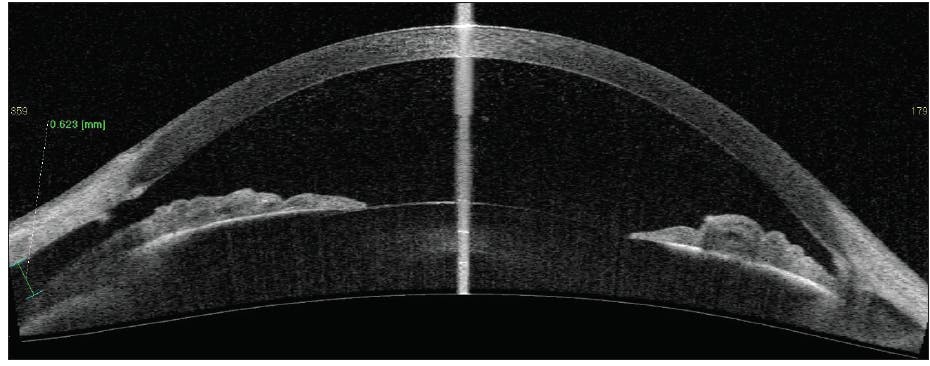

At 5 weeks postoperatively, early superficial macular folds were evident, BCVA was 20/50, and IOP was 2 mm Hg. Steroids were stopped, and atropine was continued. At 10 weeks postoperatively, BCVA was 20/70, IOP was 5 mm Hg, and OCT imaging revealed deeper macular folds and optic nerve head swelling. At this point, given the persistent hypotony maculopathy and decreasing BCVA, more invasive treatment options were considered. However, AS-OCT showed a continued reduction in both cleft size (14º) and effusion height (174 μm; Figure 4). This objective and quantifiable anatomic improvement on serial imaging was directly responsible for our decision to continue with conservative management.

Figure 4. At 10 weeks after GATT, AS-OCT showed a continued reduction in cleft size (14º) and effusion height (174 µm).

Courtesy of Thomas A. Berk, MD, and Hady Saheb, MD, MPH, FRCSC